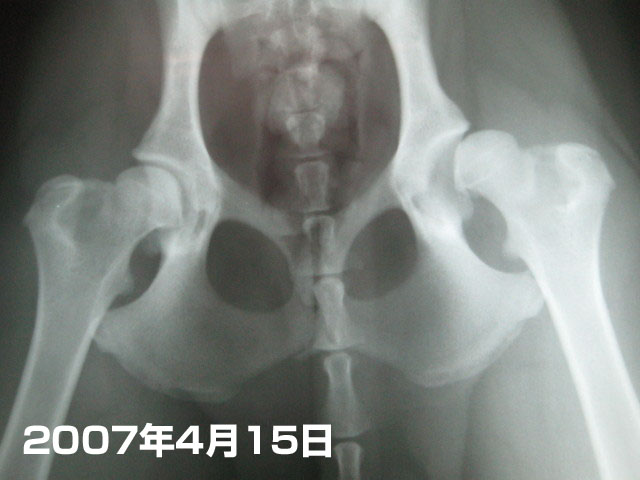

今度はもいたんの股関節。

これは2007年4月15日。後とあんよがつけなくなって痛くなった時のもの。

ほとんど亜脱臼気味(;>_<;)

で、これは本日。

どうだいp(`ー´)q かなり良くなってるでちょ〜〜!!!!!!!\(^ω^\)( /^ω^)/

成長期だから、これから良くなる可能性もあるって先生がおっしゃってたけど....ママは内心、悪くなることはあっても良くなることはないんじゃないのぉ〜(´ヘ`;)......って実は思っていたの。

でもそれははずれたね〜(^-^)v

まっ、4枚目も5枚目も麻酔をかけて撮った物じゃないのでガッチリ正確ではないかもしれないけど、様子をみるには十分ね。